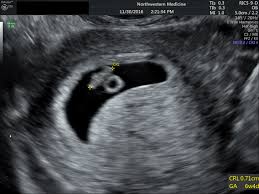

They only do abdominal scans! It is suggested that a 7 week scan followed by a 10 week scan is the optimum care for women who have experienced recurrent miscarriages. The dating scan usually takes about 30 minutes (nhs 2015a, healthlink bc 2019, sogc 2019). An ultrasound is performed at this stage of pregnancy to confirm your due date, confirm if you are having singles, twins or more and to visualise your baby's heart beating. It's very hard for them to measure when it's that small. Pregnancy dating is only an estimate, and doing an ultrasound just a couple of days too early can mean unnecessary concern and worry about not seeing the baby's heartbeat. Early pregnancy symptoms (at 7 weeks). Has this happened to anyone else? But it may still be too early in your pregnancy for a heartbeat to be found. Is 7 weeks too early to do dating ultrasound?: I will be super worried for the whole trip till. A dating scan might be recommended before 12 weeks to confirm your due date if you are unsure of your last menstrual period or your date of conception. But on the other hand, i also worry about what if i can't see the heartbeat.

The earliest you can see a heartbeat is at five weeks and two days gestation, says kinnear. Be aware, though, that sometimes 6 weeks is too early to tell. The best time to have a scan is from about 7 weeks' gestation when it should be possible to see the baby's heartbeat in a normal pregnancy. At our clinics we scan from 7 weeks but at this time due dates are not totally accurate as it is very early stages. I will be super worried for the whole trip till. You can discuss whether you want or need a dating scan with your doctor or midwife. I am so dissapointed but will go back in 2 weeks for another scan. Because a ton of gestational development happens between 7 and 12 weeks, making an early ultrasound a completely different experience than the traditional one in your first trimester.

It is usually done to check how many weeks pregnant you are and therefore to calculate the estimated due date, but it can be done for other reasons. A dating scan might be recommended before 12 weeks to confirm your due date if you are unsure of your last menstrual period or your date of conception. Wait one week more for your dating scan and see how much baby changes. But after seen ur pics and advice on early scans i wanted some advice please! Did anybody get an abdominal ultrasound at 7 or 8 weeks along? We should be able to see a heartbeat from 6 weeks. A pregnancy can be seen on scan from as early as 6 weeks from the first day of your last period (lmp). But it may still be too early in your pregnancy for a heartbeat to be found. You will be offered your first dating scan at 8 to 14 weeks. Early scan at 7 weeks. It is suggested that a 7 week scan followed by a 10 week scan is the optimum care for women who have experienced recurrent miscarriages. Reasons for an 8 week ultrasound. The dating scan usually takes about 30 minutes (nhs 2015a, healthlink bc 2019, sogc 2019).

But it may still be too early in your pregnancy for a heartbeat to be found. Before i booked i asked the doctor when i should go and he said to go as soon as possible. Early scan at 7 weeks. But on the other hand, i also worry about what if i can't see the heartbeat. Theoriginallea77 shares her positive early internal vaginal scan experience. You may be referred for an early scan because of vaginal bleeding or spotting, or possibly because you have had problems in a previous pregnancy. I will be between 7 and 8 weeks at the scan (based on lmp i will be 7w2d but my hcg at. I had a 7 week scan which showed about 6+5, then a 10 week which measured as 9+1. Hi all, im 6 weeks today and just went to have my dating scan. Hi i dont normally post on here! The dating scan will determine a number of things including: In reality, there are many reasons your doctor may want an early scan. Has this happened to anyone else?